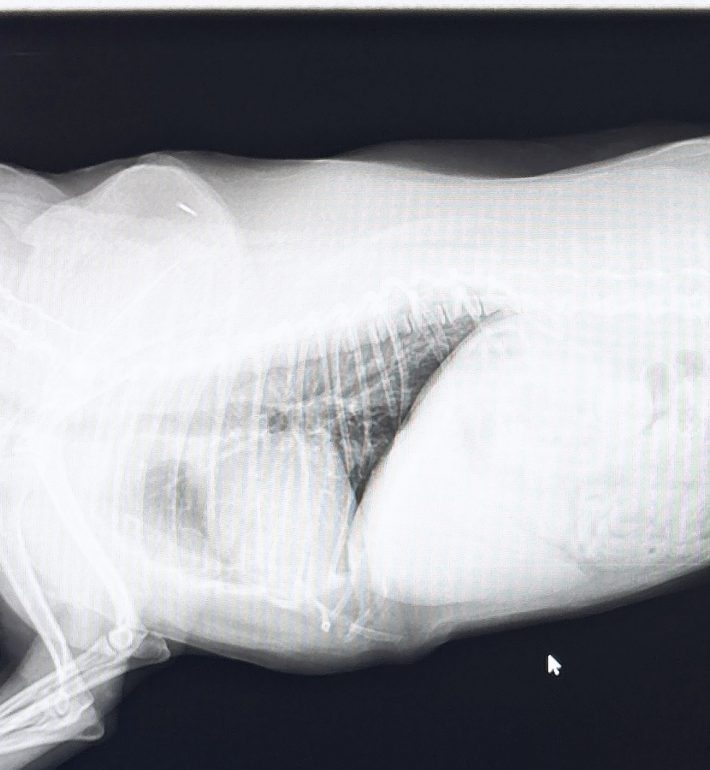

レントゲン検査…通常のレントゲン検査では肺は黒く写るが、肺炎になっている場合は白く写るので肺炎の重症度など見ることができる

○横から撮影したレントゲン画像

(それぞれ画像は左側が首側、右側がお腹側)

通常の肺

(画像の中央辺りが黒い)

肺炎により異常を起こしている

(通常の肺と比べ黒い部分がない、または少ない)